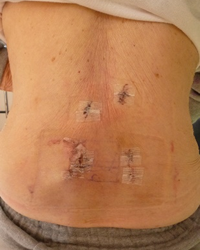

椎間板ヘルニアでは椎間板の中の髄核と呼ばれる部分が神経を圧迫し、腰痛や下肢の疼痛、痺れ、筋力低下などの症状を引き起こします。MEDは内視鏡を使用し、症状の原因となっている髄核を取り出す手術で、従来の方法より切開が小さく16mmの切開となっておりますので、痛みが少なく早期の退院・社会復帰が可能となっております。当院の入院期間は1泊2日となっております。

当院では低侵襲の手術方法を採用し創が26mmと小さい切開で実施しております。

従来の大きく切開する手術方法よりも術後の痛みは少なく、入院期間は4泊5日と早期の退院・社会復帰が可能です。